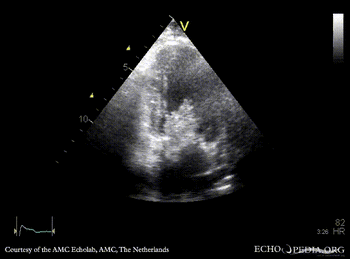

Giant myxoma in left atrium

M-Mode through mitral valve

PSAX